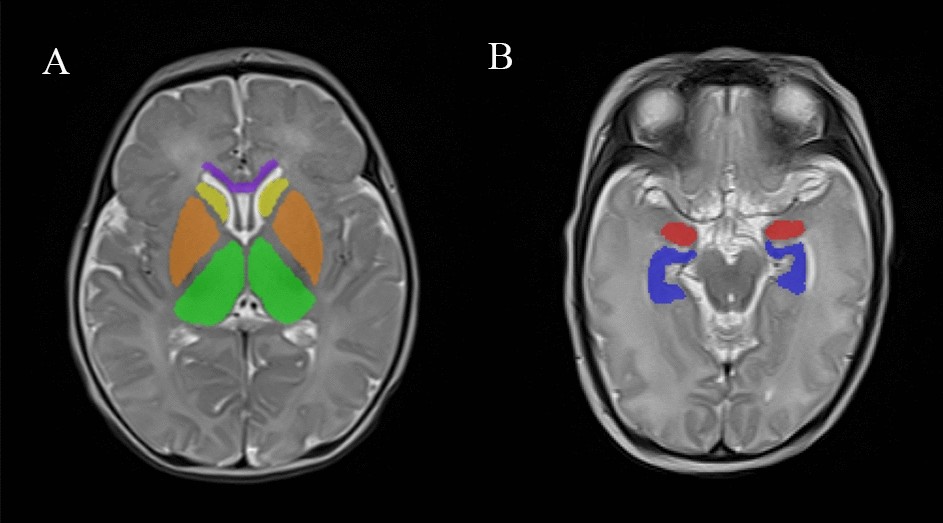

Figure 4

Example of a delineation of the investigated cerebral structures on T2W images. The different brain regions are represented by different colors. Purple represents the genu of the corpus callosum, yellow represents the caudate nucleus, orange represents the lenticular nuclei, green represents the thalamus, red represents the amygdala and blue represents the hippocampus.